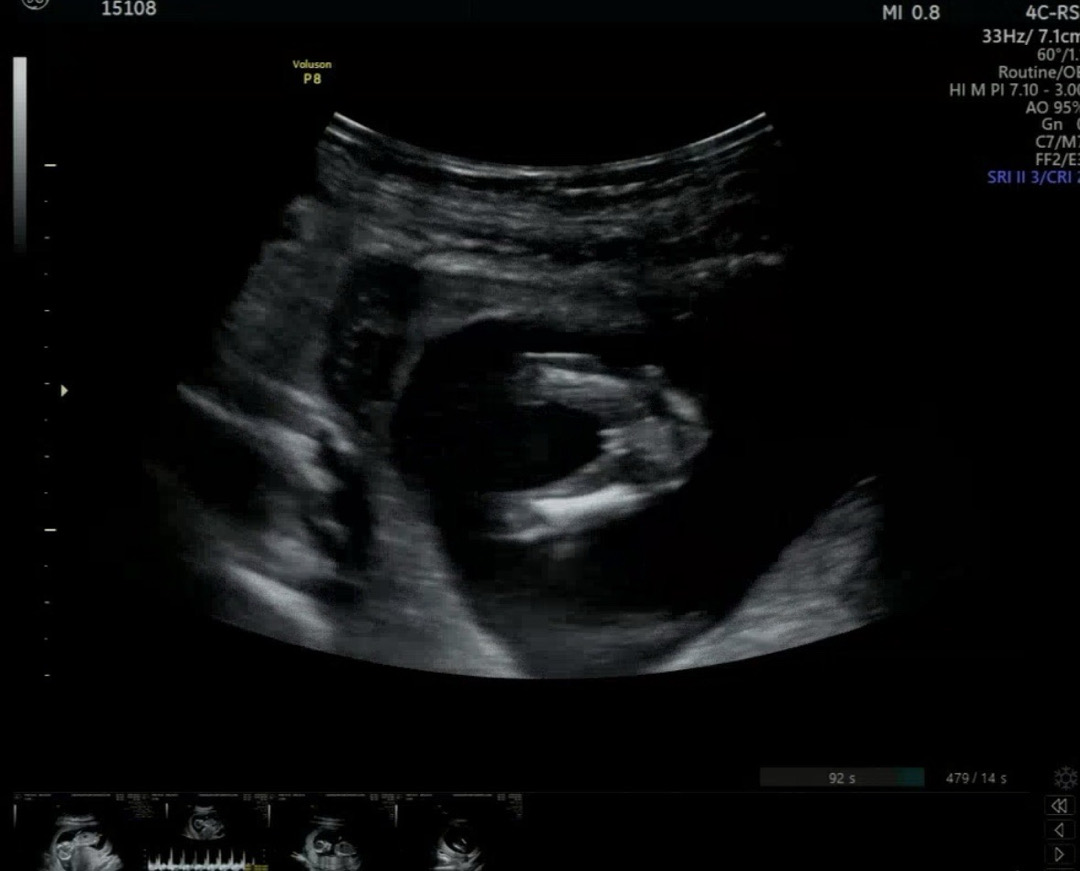

다리사이 삼지창(튤립) 딸일까요 ...?

13주차중반입니다 성별 뭐일까요?